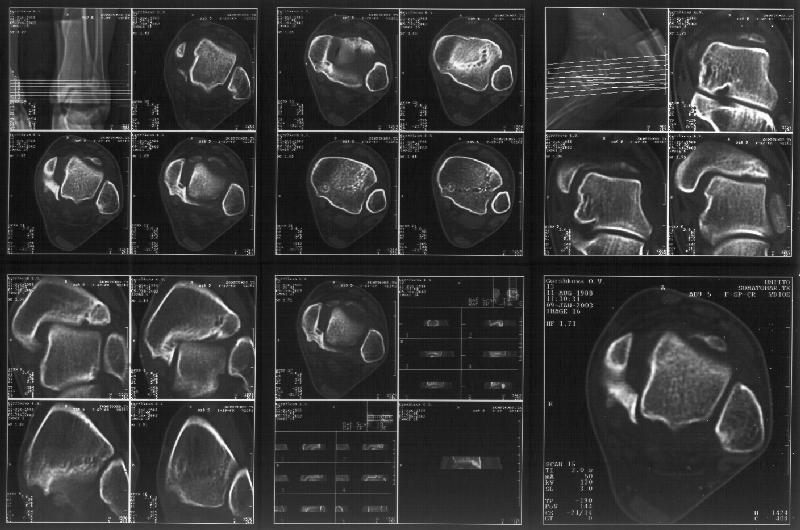

Я пометил линию перелома черной линией.

К сожалению на последних присланных срезах КТ нет более низкого, через таран, среза, который был на прежнем майле. На XR я попытался показать

стержень внутри сустава и то как он раскрывает пространство между тараном и мед. малеолом.

Сегодня пациентке сделали сравнительную КТ. А ксиальные и Фронтальные срезы приложены. Ваше мнение?

Фронтальные

Аксиальные

Отправитель: Й. Воск 19 Январь 2003, 22:50

На КТ я попытался изобразить скромными своими способностями (А)- место перелома, (С)- нормальный суставной зазор меж тараном и тремя его маллеолами. (В)- образовавшийся в результате перелома широкий раза в три зазор, позволяющий, по-моему, сублюксацию тарана при ходьбе. В свете данных КТ, критически важных, я бы предложил вертикальную остеотомию места перелома

задне-внутренним подходом и фиксацию мед. маллеола прижатым к тарану с помощью тонкого compression screw. После этого гипсовый сапожок и немедленное расхаживание ноги.